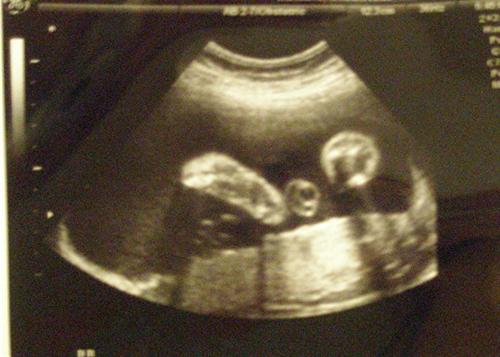

Here are some pics. We couldnt get a face shot because of her position:

Lizard Baby returns:

DD was breech for a long time, but turned in time for her birthday. LOVE the Lizard Baby comment- I have always thought the same thing when I have my sonos!

Nice spine!!!